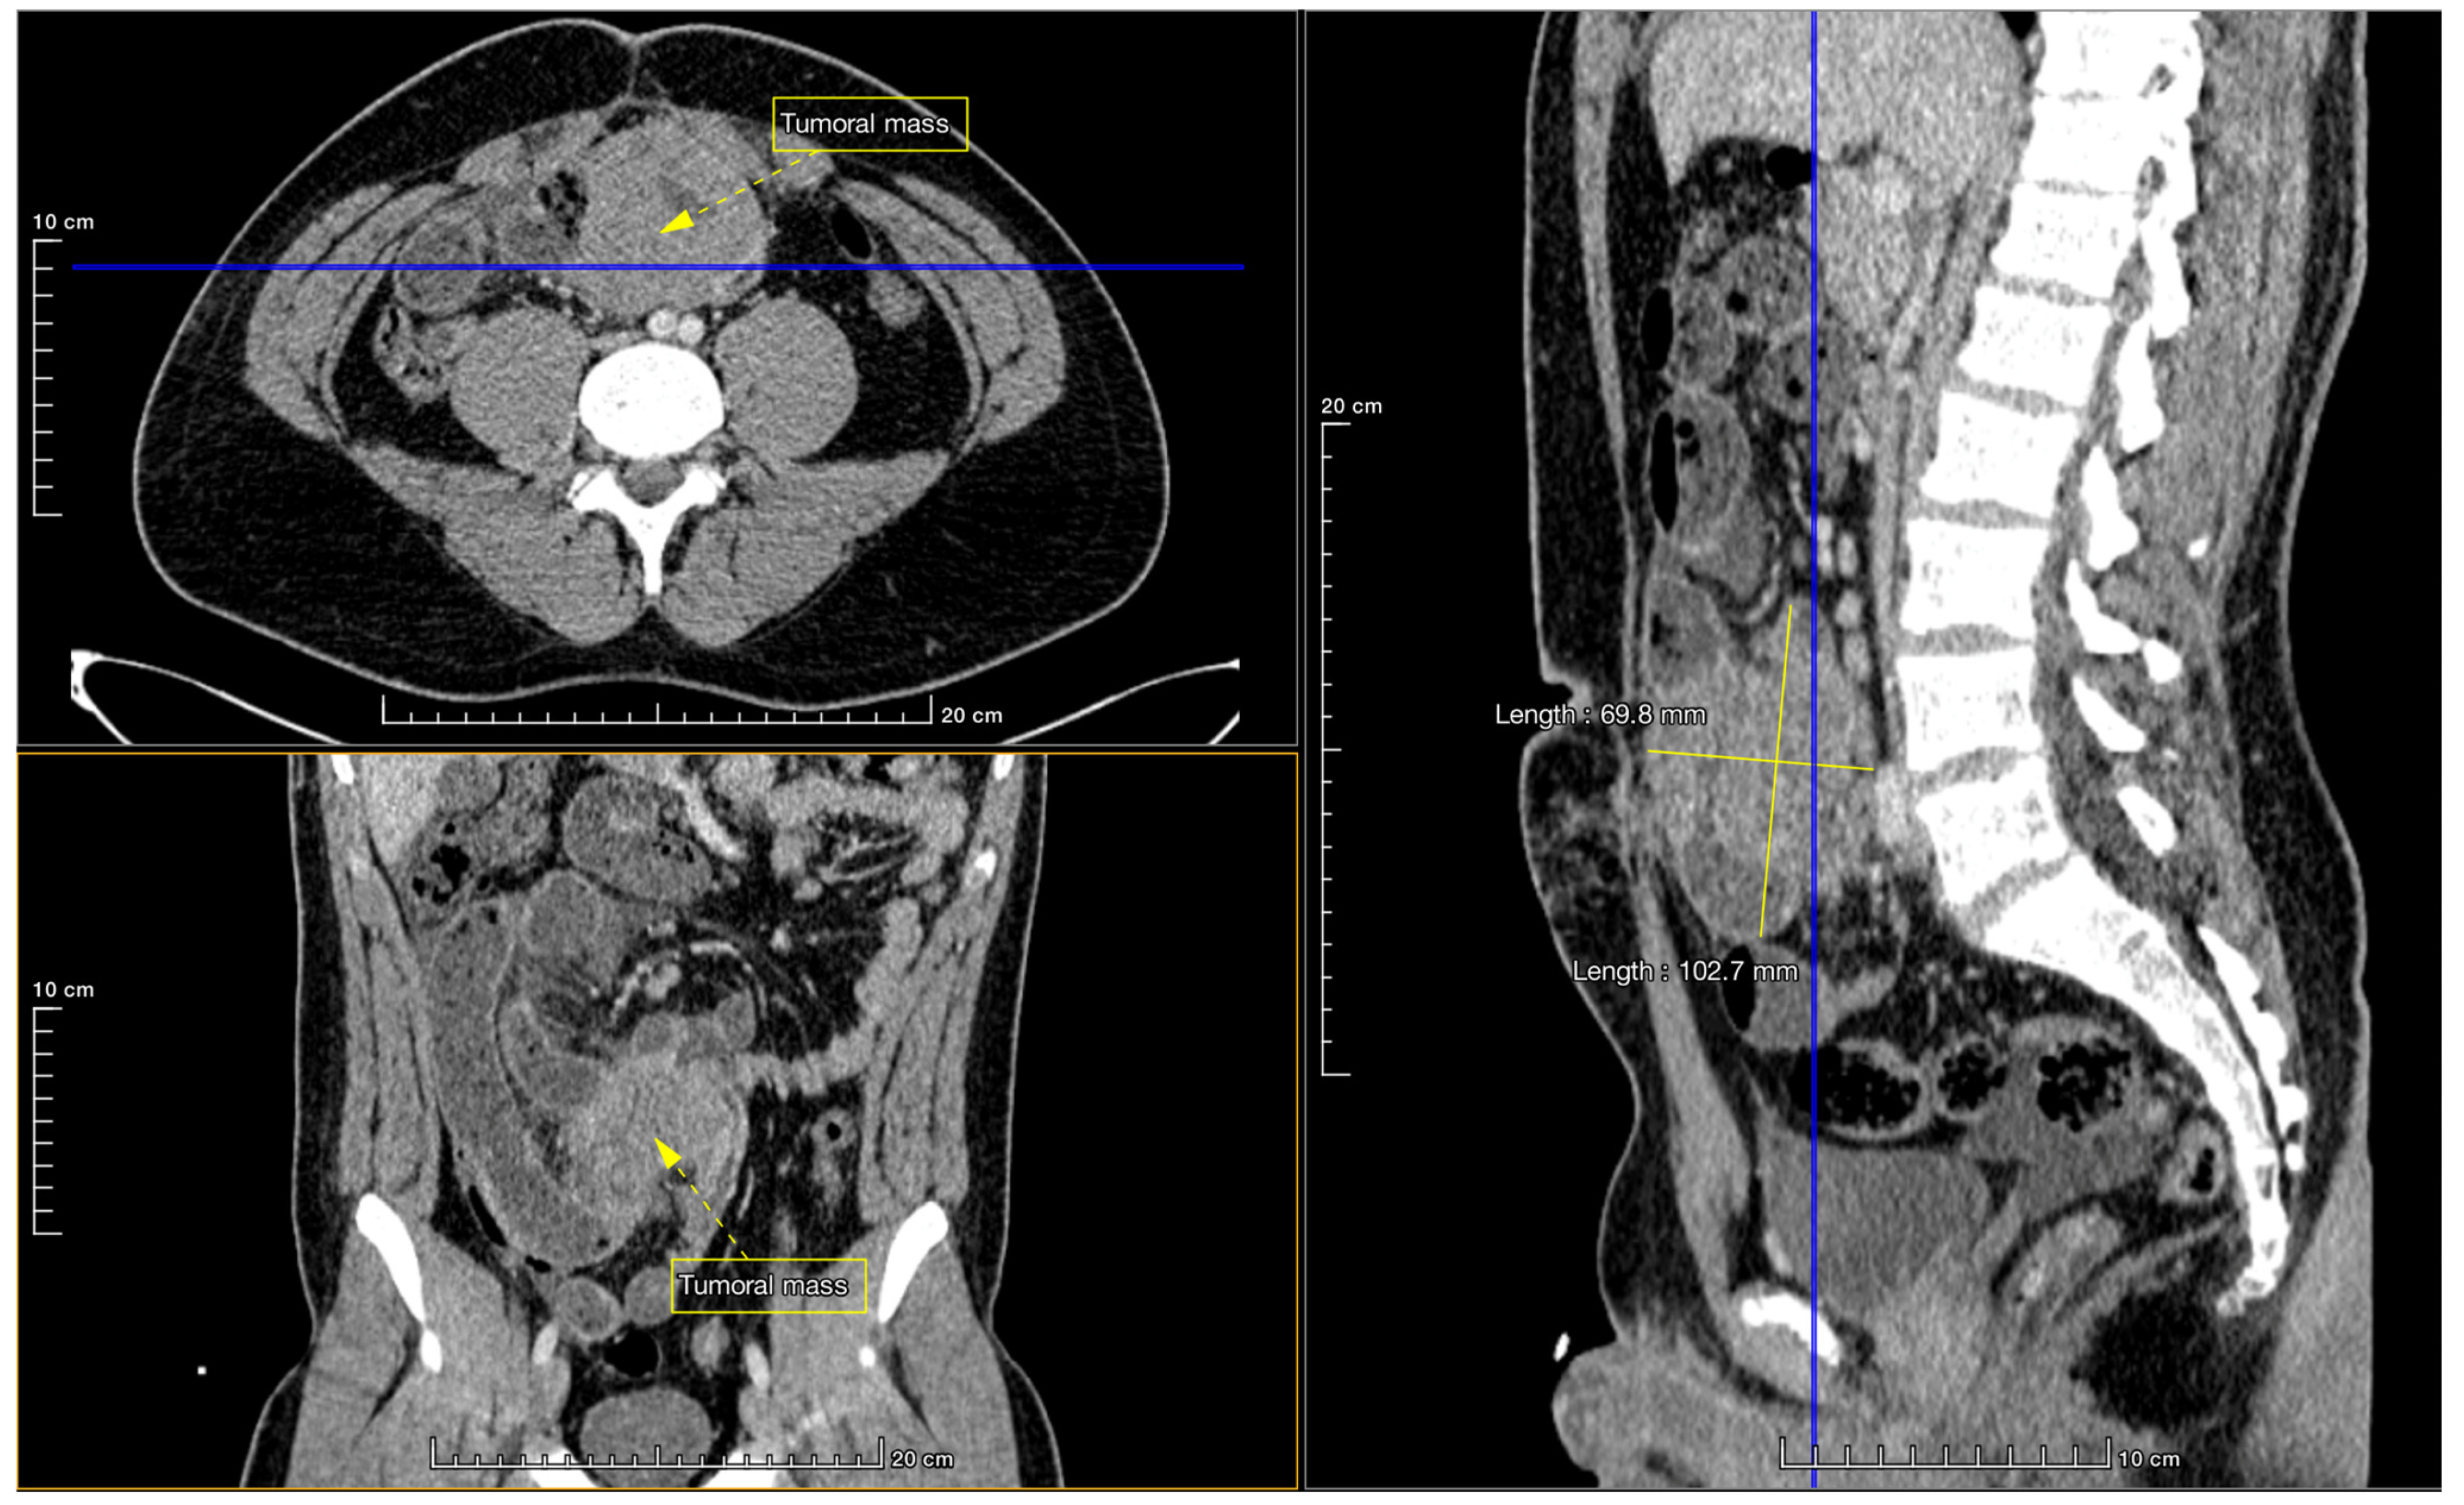

Successful Laparoscopy-Assisted Extirpation of Burkitt’s Lymphoma Causing Intestinal Obstruction in a 17-Year-Old Boy

2. Case Report